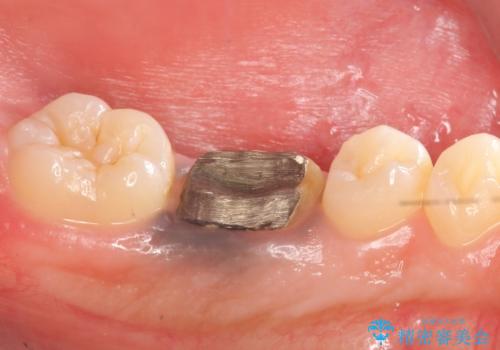

- 他院にて治療途中の歯を診て欲しいといらっしゃった方の症例です。

X線上で根尖病変を認めたため再根管治療を行い、オールセラミッククラウンによる補綴を行いました。